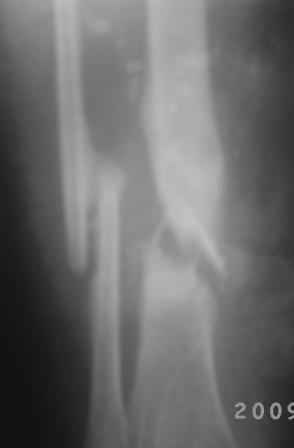

Посттравматический ложный сустав б/берцовой кости.

Добрый вечер, уважаемые коллеги! Обратилась женщина, 30 лет. ДТП 11 октября 2008 г. Из выписки: О/многооскольчатый перелом костей левой голени по Каплану 3В,

ПХО раны, гипсовая повязка, перевод в гор.б-цу, в 21.10.08г КДО аппаратом Илизарова(почему-то в вальгусном положении), ч-з два месяца тромбофлебит лев.н/конечности, отеки, воспаление, и аппарат сняли, с тех пор ходит в гипсовой повязке со стременем. к-рую периодически меняют, якобы кость со временем срастется.

На уровне н/з голени глубокие рубцы по передне-медиальной поверхности, умеренная отечность голени, незначительная патологическая подвижность, умерен. болезненность, ось правильная, укорочение 1,5см.

Наш план БИОС после остеоклазии м/берцовой кости. Но укорочение еще будет увеличиваться!